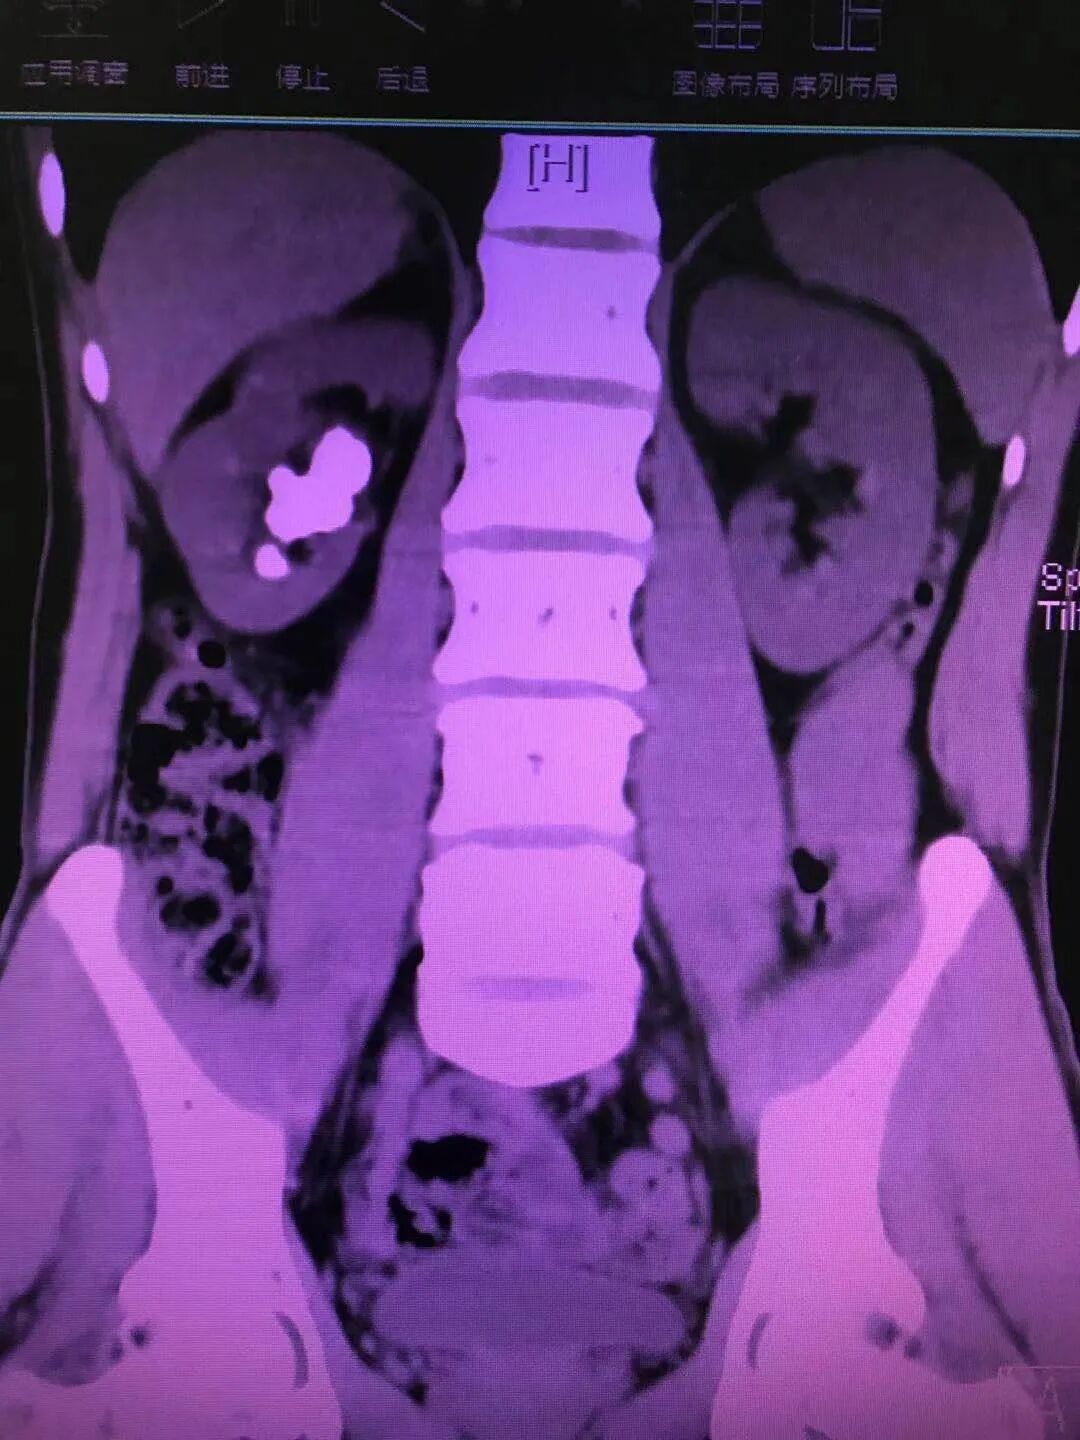

今年1月,医院外一科收治了一名40多岁的男性患者。该患者因腰部绞痛难忍,前来医院就诊。以刘文庭医生和尹曦医生为代表的外一科团队在对病人查体后发现,患者右肾结石散在且多发,结石密度影,肾实质厚,肾囊肿巨大且多发,手术难度颇大。

经过外一科医护团队对患者病情的仔细分析和详细论证,终于设计出一条适合患者病情的风险最小的手术治疗方案,即经皮肾囊肿输尿管软镜下右肾结石钬激光碎石术;利用此技术,将患者复杂性肾结石和肾囊肿通过同一通道经皮肾贯穿囊肿先内引流,再由内引流孔进入肾盂,最后利用钬激光进行碎石。患者利用此新技术前后共进行了两次碎石手术,手术治疗效果良好。第二次碎石手术顺利完成后,患者体内95%的结石碎石成功并成功排除体外,其病情已得到明显好转,目前已康复出院。